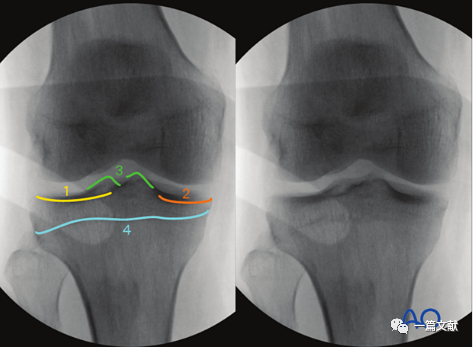

2)标准正位的评估:1、髌骨下极位于股骨双髁之间 2、腓骨头的1/4-1/3被胫骨外侧平台遮盖。如下图:

3)解剖标志的识别:如下图:1、外侧胫骨平台关节面 2、髌骨 3、腓骨头4、内侧胫骨平台5、外侧髁间脊6、内侧髁间脊。

4)标准正位的意义:1、评估关节内骨折块复位情况(关节面台阶)2、检视关节内的游离骨块或突入关节的内植物3、内翻或外翻应力下关节间隙变化情况(侧副韧带损伤指征)4、髁间脊撕脱骨折的评估(叉韧带损伤情况)5、评估胫骨关节线和胫骨轴线之间的角度(85-90°)。